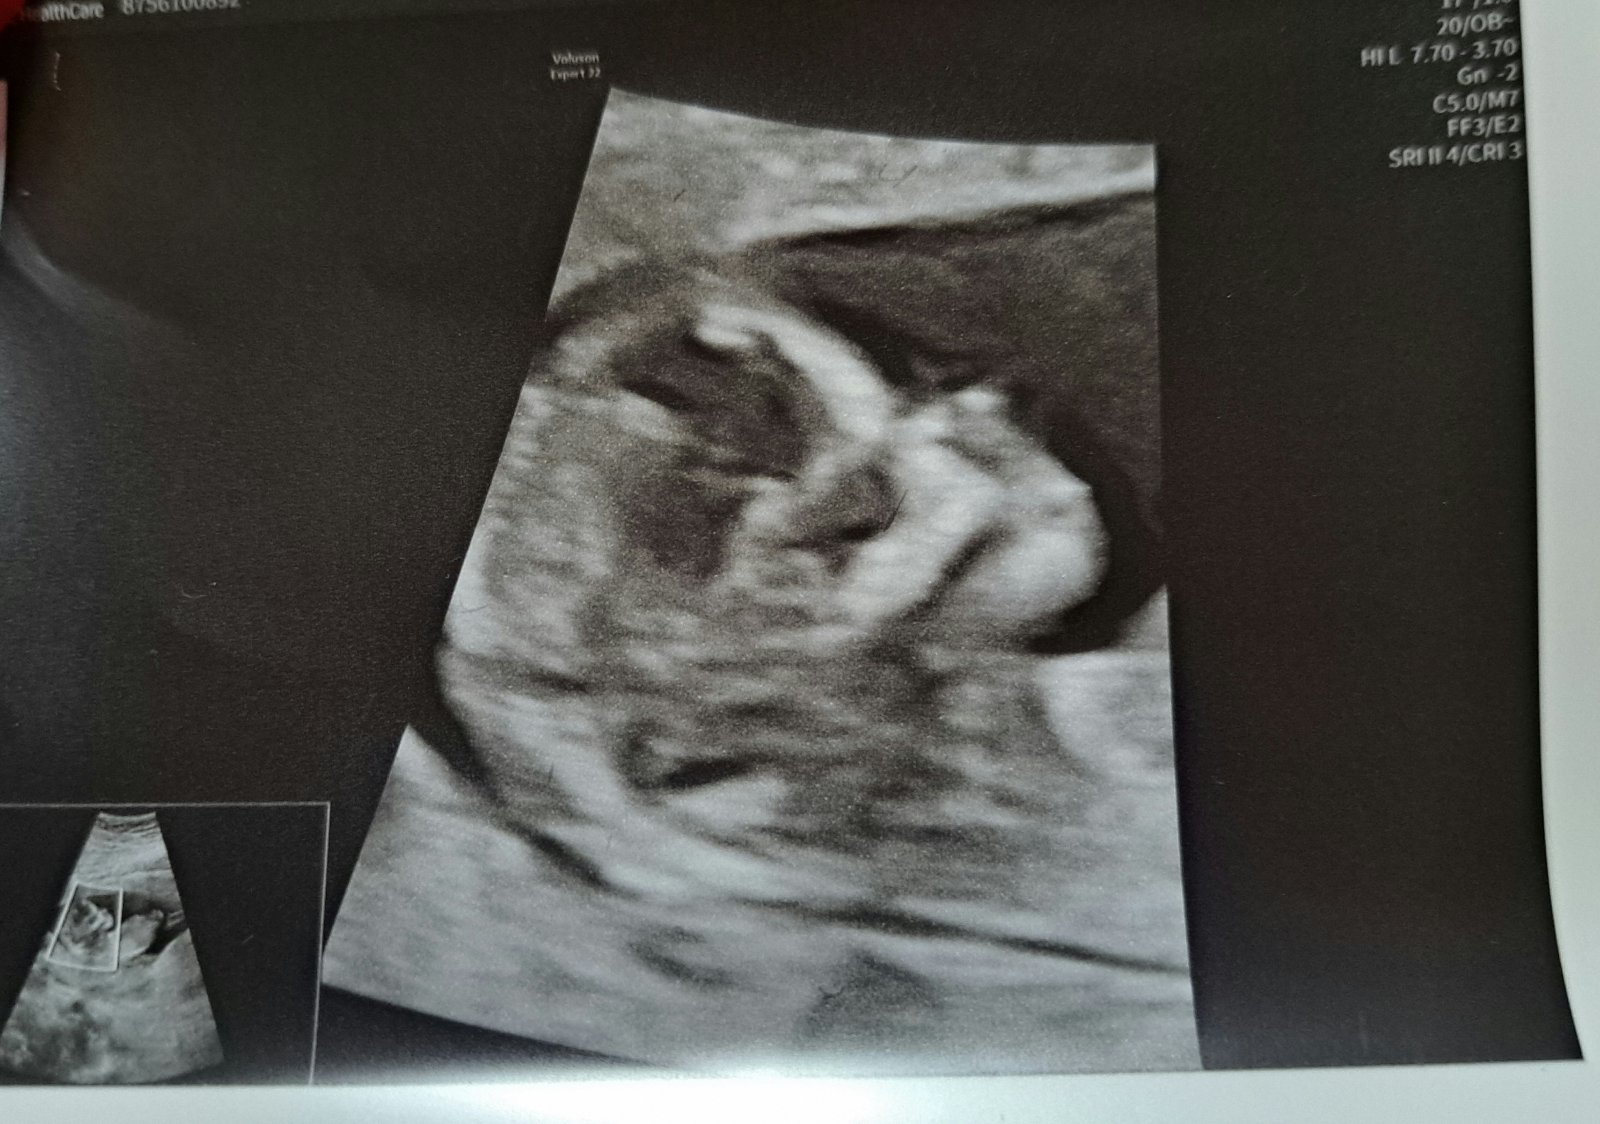

Naše krásná bublinka 🥰💞❤️🍀🍀🍀🍀